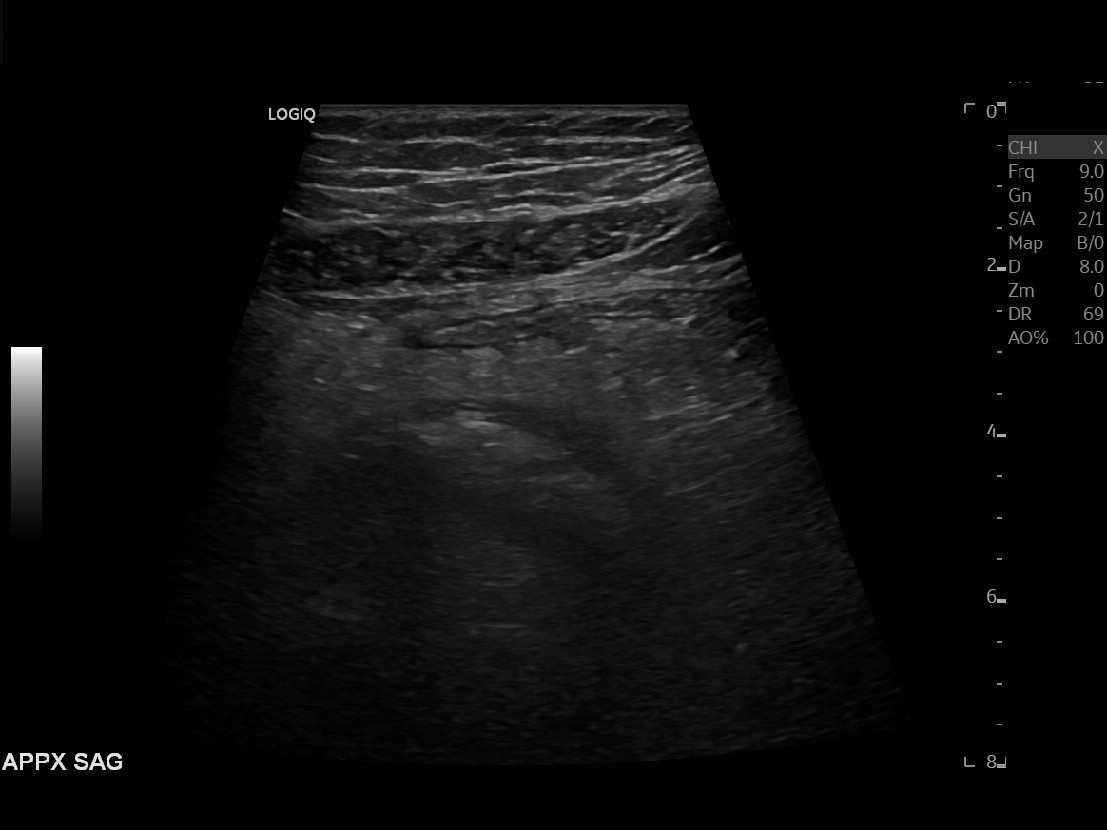

Appendicitis 17

Difficult to image perforated appendicitis with fat stranding and free fluid